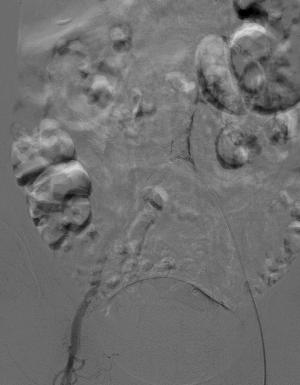

释放后造影

术后患者跨瓣压差由79改善为低于10,术中造影剂控制在120ml以下,气管插管下患者无明显过敏反应,术后加强利尿,患者顺利苏醒,第二天即可下床活动。